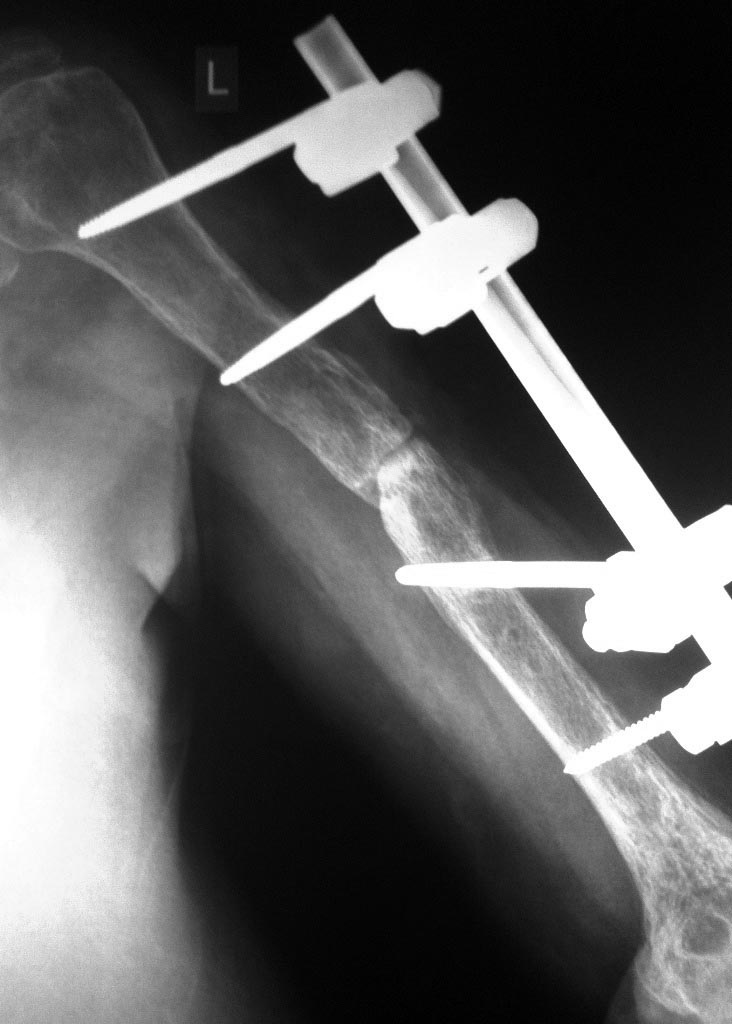

Обратилась пациентка с ложным суставом средней трети левого плеча

стабилизированный в стержневом АВФ.

анамнез - 01.01.16г. получила закрытый перлом средней трети левой

плечевой кости.

05.01.16г. оперирована - МОС пластиной;

20.01.16г. вскрытие нагноившейся гематомы плеча;

16.02.16г. - удаление металлоконструкции, стабилизация АВФ левой

плечевой кости (по выпискам по поводу хронического остеомиелита);

20.04.16г. - костная пластинка зоны перелома, перемонтаж АВФ.

Сейчас - кожный покровы без признаков восполнения, температура в

пределах нормы на протяжении всего периода после закрытия раны (с

февраля), свищей не было. Локтевой без контрактуры, в плечевом есть

ограничение объёма движения.На Rg - признаки атрофического ложного

сустава, локунарный остеопороз (секвестров либо периотсальной реакции

вроде бы как нет). Рассматриваем вариант БИОС+костная пластика (если не

удастся закрыто), но вот данные в медицинской книжке об перенесённом

остеомиели